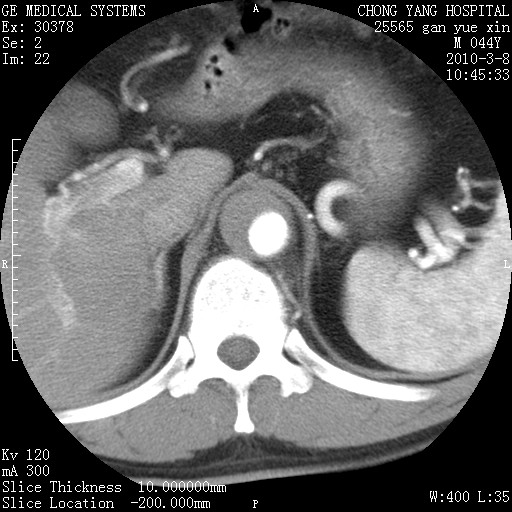

标题: CT24940:主动脉增强,典型病例。 [打印本页]

标题: CT24940:主动脉增强,典型病例。

夹层动脉瘤。

动脉夹层

夹层动脉瘤,典型

主动脉夹层。

动脉夹层的分型:

⒈debakey分型:根据主动脉夹层累及部位,分为三型:ⅰ型:原发破口位于升主动脉或主动脉弓部,夹层累及升主动脉、主动脉弓部、胸主动脉、腹主动脉大部或全部,少数可累及髂动脉。ⅱ型:原发破口位于升主动脉,夹层累及升主动脉,少数可累及部分主动脉弓。ⅲ型:原发破口位于左锁骨下动脉开口远端,根据夹层累及范围又分为ⅲa,ⅲb。ⅲa型:夹层累及胸主动脉。ⅲb型:夹层累及升主动脉、腹主动脉大部或全部。少数可累及髂动脉。

⒉stanford分型:a型:夹层累及升主动脉,无论远端范围如何。b型:夹层累及左锁骨下动脉开口以远的降主动脉。

夹层动脉瘤,少量胸水

夹层动脉瘤;左侧少量胸腔积液。

典型主动脉夹层。